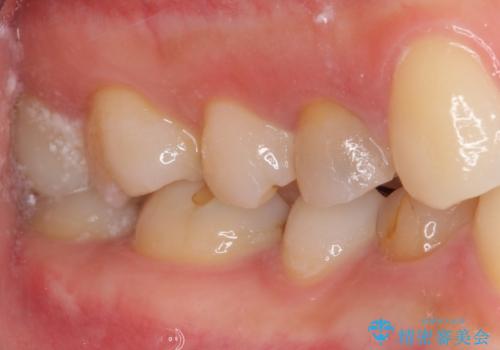

ジルコニアカスタムアバットメントは、歯肉ラインに金属が見えにくいというだけでなく、クラウンを装着する土台の形が天然歯と近い形態となるため、清掃性が高く歯肉が腫れにくいというメリットがあります。

インプラントは、人工骨を用いた際の骨誘導能が比較的高いとさせるストローマン社のSLActiveを使用しました。